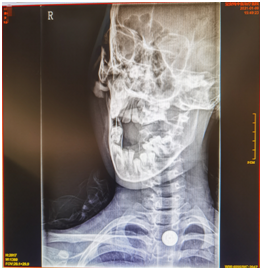

辅助检查:2021-01-09我院颈椎正侧位+开口位:颈椎轴线右侧旋转、侧弯,生理曲度轻度反弓。